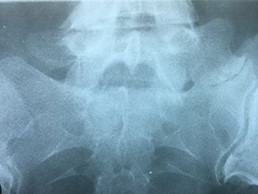

A 42-year-old female presented to the clinic with a history of chronic low back pain. She reported no relevant medical history. She had already been treated in the last 4 years by general practitioners with analgesics and home based physiotherapy with no satisfactory results. She had two previous admissions to the emergency department where morphine was prescribed to control the pain on her lower back. She was under ambulatory treatment with diclofenac, and tizanidine with partial relief of symptoms. Her main complaint was pain on the lower lumbar back with no radiation to the lower extremities. In her physical evaluation she presented limitation to full rotation and bending of the lumbar spine due to pain. Lasegue sign was negative, sensitivity, reflexes, sagittal balance, distal muscular strength and pulses were normal. Radiographs showed an overdeveloped left transverse process of the fifth lumbar vertebra which contacts with the sacrum at the left sacral wing with signs of degeneration at the same site (Fig. 1). Magnetic resonance imaging (MRI) studies were obtained (Figs 2–5). The patient was taken to the operating room where infiltration with 1 mL of lidocaine and 40 mg of Triamcinolone was performed in the pseudoarticulation between the left transverse process and the sacrum under fluoroscopic guidance. She reported a complete relief of pain after the procedure. At three months follow-up she was managed with strengthening and stabilizing exercises for the lumbar spine and postural education was initiated. She remains asymptomatic at her 12 months follow up.

Radiographs showing an overdeveloped left transverse process, which contacts with the sacrum left sacral wing (Castelvi’s Type IIa).

Plain radiographs of the lumbosacral spine demonstrate 76–84% effectiveness to detect LSTV. Ferguson radiographs of the lumbosacral spine (AP radiograph with a 30° cranial angulation) presents with a higher sensitivity in detecting LSTV. Mid-sagittal T2-weighted MRI presents with 80% sensitivity and specificity for the diagnosis, with bone marrow edema as one of the most common findings [5]. CT scan is a complimentary imaging resource that helps defining bone structures, osteophytes and the state of the pseudoarticulation of the fifth transverse process [6].